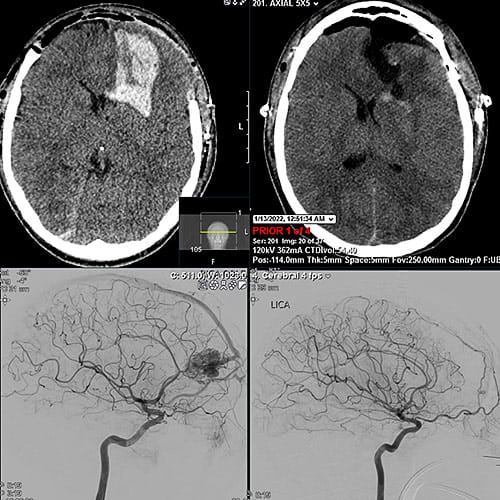

Convulsing in spasms, he was taken by paramedics to Southwest General Health Center, the closest hospital to his Columbia Station home. A CT scan of his brain showed a ruptured AVM, and a medical helicopter was called to transport Joshua to UH Rainbow, where a team of fellowship-trained pediatric neurosurgeons were waiting.

A CT scan of Joshua’s brain showed a ruptured arteriovenous malformation

Joshua’s ruptured AVM occurred in his left frontal lobe, the section of brain that largely controls language and cognition. Dr. Tomei had to remove the front part of his skull to operate on the blood clot. The skull is left off for several days to prevent further injury when his brain swells during recovery in the Pediatric Intensive Care Unit.

Once Joshua recovered from the initial brain surgery, neurosurgeon Yin Hu, MD, performed an angiogram to essentially inject a glue-like material into the primary blood vessel feeding blood into the AVM. Then a third neurosurgeon, Abhishek Ray, MD, removed the AVM and replaced the skull a week later.